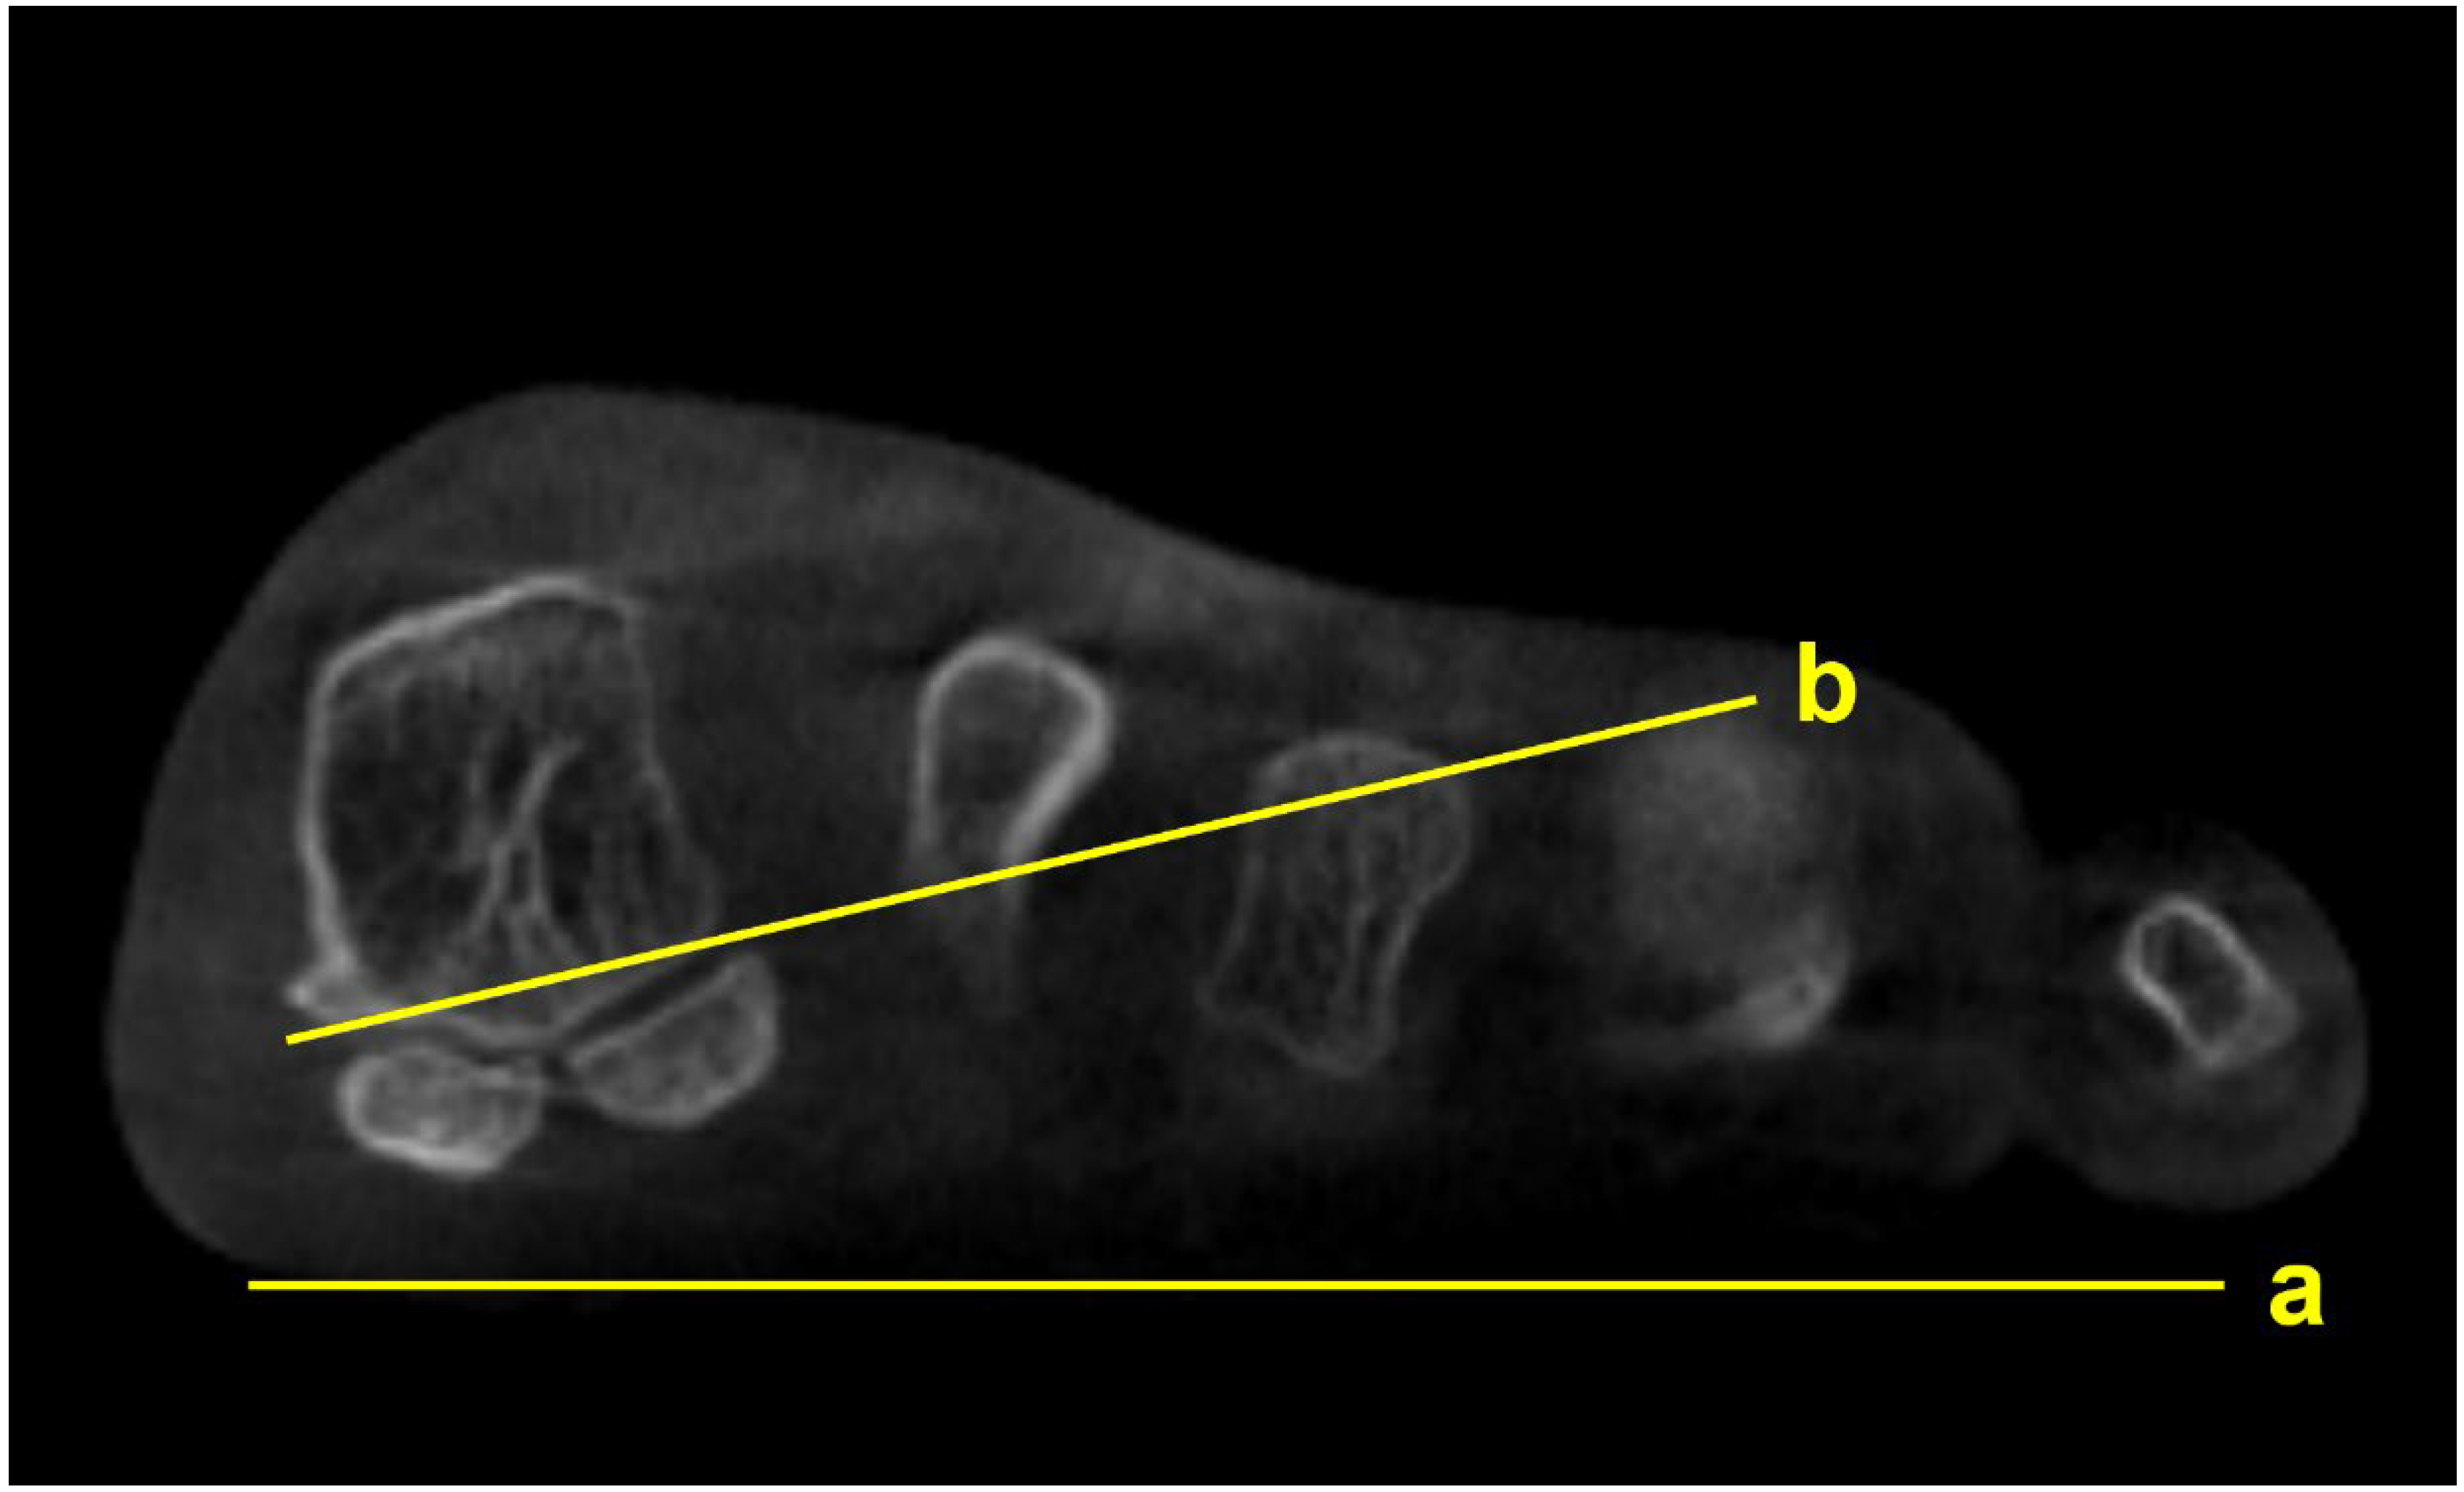

Figure 3.

M1 pronation angle (M1PA) is the angle between the floor (a) and a line drawn from the most inferomedial border of the medial sesamoid facet to the most lateral border of the lateral sesamoid facet (b).